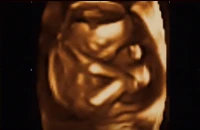

Terhesnapló10 - Liza: Kisfiúnk lesz! (19. hét)

Igazán vártuk már ezt az ultrahangot. Reménykedtünk benne, hogy végre megtudjuk a kis magzatunk nemét, és ezután nem csak krumplibabának hívjuk majd, hanem Barnabásnak vagy Juliannának.